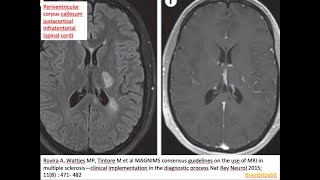

Multiple Sclerosis White Spots And Red Flags -...

39. Multiple Sclerosis...